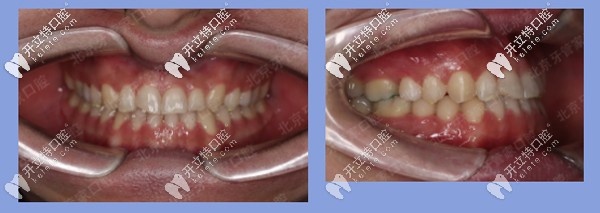

被矯治者基本信息:王先生,22歲,地包天,牙列散縫。

患者牙齒矯正前

前期檢查:反合(又稱地包天),骨性三類(lèi),磨牙關(guān)系三類(lèi)。下前牙已經(jīng)發(fā)生舌傾,存在縫隙。